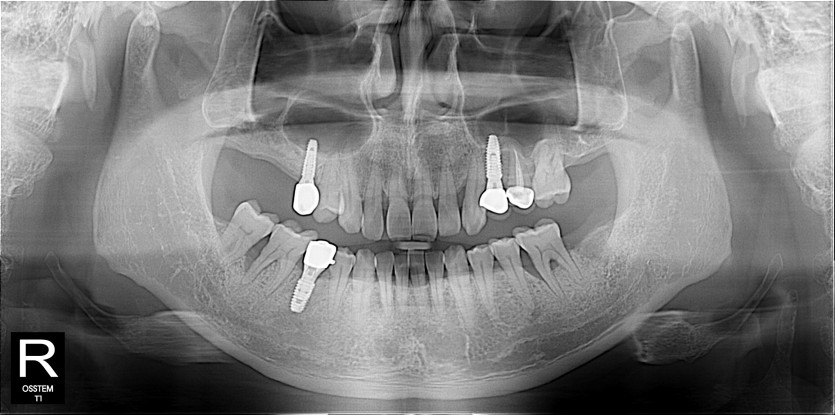

임플란트 사례